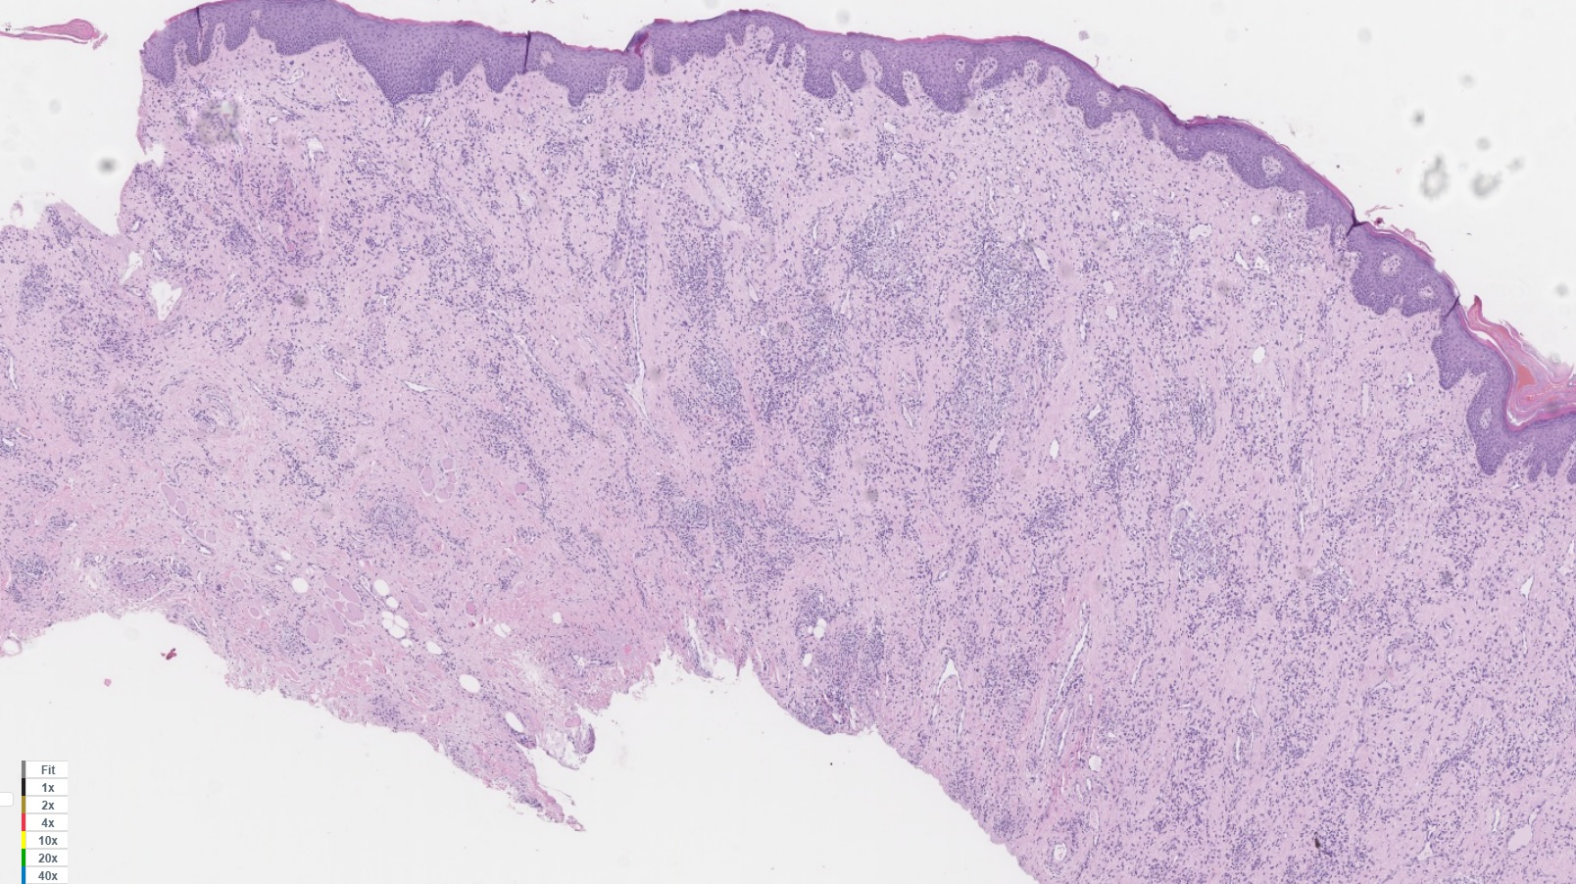

A histopathological study of the surgical specimens was undertaken, showing superficial and deep chronic perivascular inflammation associated to granulomas, consistent with orofacial granulomatosis (cheilitis granulomatosa) (Figure 4 [Fig. 4], Figure 5 [Fig. 5]).

Figure 4: In this histological image, a mucous layer with chronic lymphoplasmacitic infiltrate can be seen, with presence of noncaseating granulomas. Hematoxylin and eosin (H&E). 2x.

Figure 5: In this histological image, a mucous layer with chronic lymphoplasmacitic infiltrate can be seen, with presence of noncaseating granulomas. Hematoxylin and eosin (H&E). 20x.